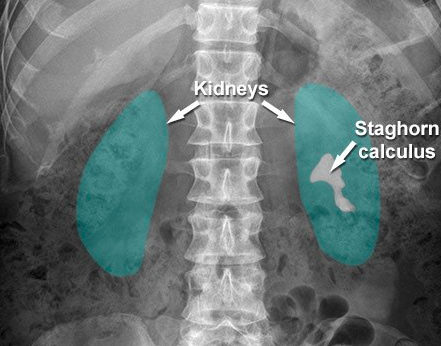

What is the cause of the abnormal calcification?

Adrenal calcification

Appendicolith

Gallstones

Pancreatic calcification

Staghorn renal calculus

A

What infection is a likely cause of this pathology? [1]

On this plain radiograph of the kidneys, ureters and bladder (‘KUB’), a large staghorn calculus can be seen in the left kidney. **Proteus infection** is often implicated and management can be difficult.